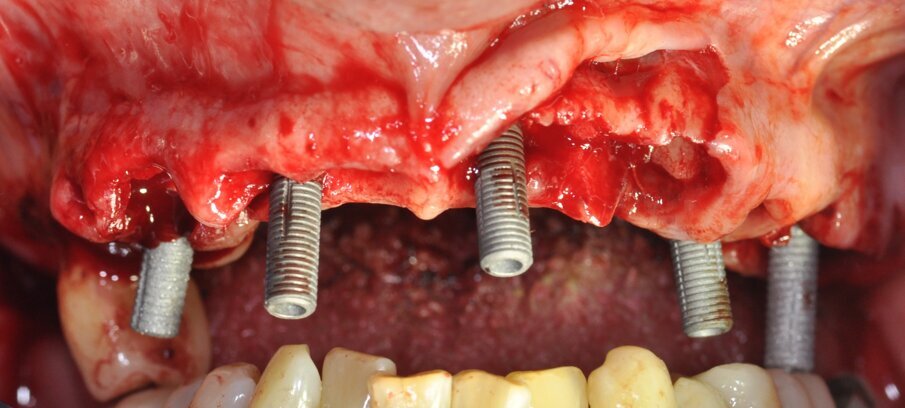

I pazienti considerati eleggibili all’inclusione erano coloro che fossero stati sottoposti a riabilitazione con protesi full-arch a carico immediato con tecnica Flat-one-Bridge (Figg. 1, 2). I pazienti, già al tempo della chirurgia, erano inclusi solo se maggiorenni, complessivamente in salute, condiscendenti alle misure di igiene orale prescritte e alle visite di controllo programmate. I criteri di esclusione erano: presenza di fattori sistemici o locali che avrebbero potuto controindicare la chirurgia, scarsa igiene orale, abitudine al fumo di più di 10 sigarette al giorno, gravidanza, storia di dipendenza e/o abuso di sostanze stupefacenti e/o alcool.

Tutti i pazienti sono stati trattati con tecnica FoB su almeno 5 impianti con superficie Ossean (Intra-Lock) raggiungendo un torque non inferiore a 35 Ncm (Fig. 3). Gli impianti in questione presentano una superficie nano-irruvidita con Calcio e una macro-geometria che ben si adatta al carico immediato15, 16. In particolare, il disegno conico facilita l’ottenimento della stabilità primaria ed è stata associata a una osseointergazione precoce della fixture nelle prime settimane17.

Fig. 3_Foto intra-orale durante il posizionamento degli impianti nell’arcata superiore.